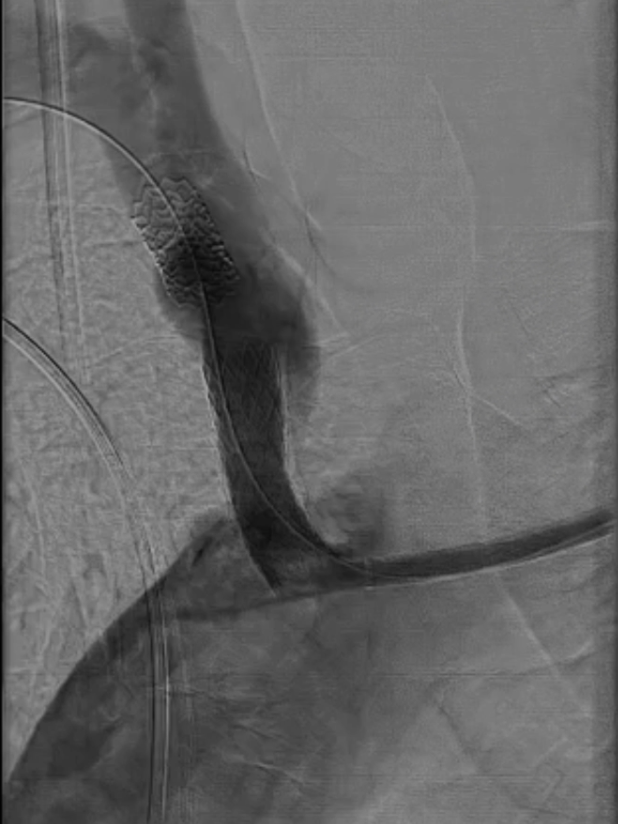

支架置入:通过“球囊带鞘”技术跟进长鞘至支架远端,采用同轴双导丝技术送入VBX8×29mm球扩覆膜支架,多角度造影定位后释放。

撤球囊时更进长鞘

至支架远端

同轴双导丝技术送入

VBX 8*29mm球扩覆膜

支架反复造影定位

释放支架

收尾操作:再次以球囊带鞘方式跟进长鞘至支架远端,回收保护伞;最终造影显示支架内血流通畅,右锁骨下动脉、右颈动脉、椎动脉显影良好,椎动脉血流速度较术前明显改善。

长鞘上行困难

回收保护伞

再次球囊带鞘

更进至支架远端

造影支架内通畅

右锁骨下动脉 右侧颈动脉

血流通畅椎动脉显影好